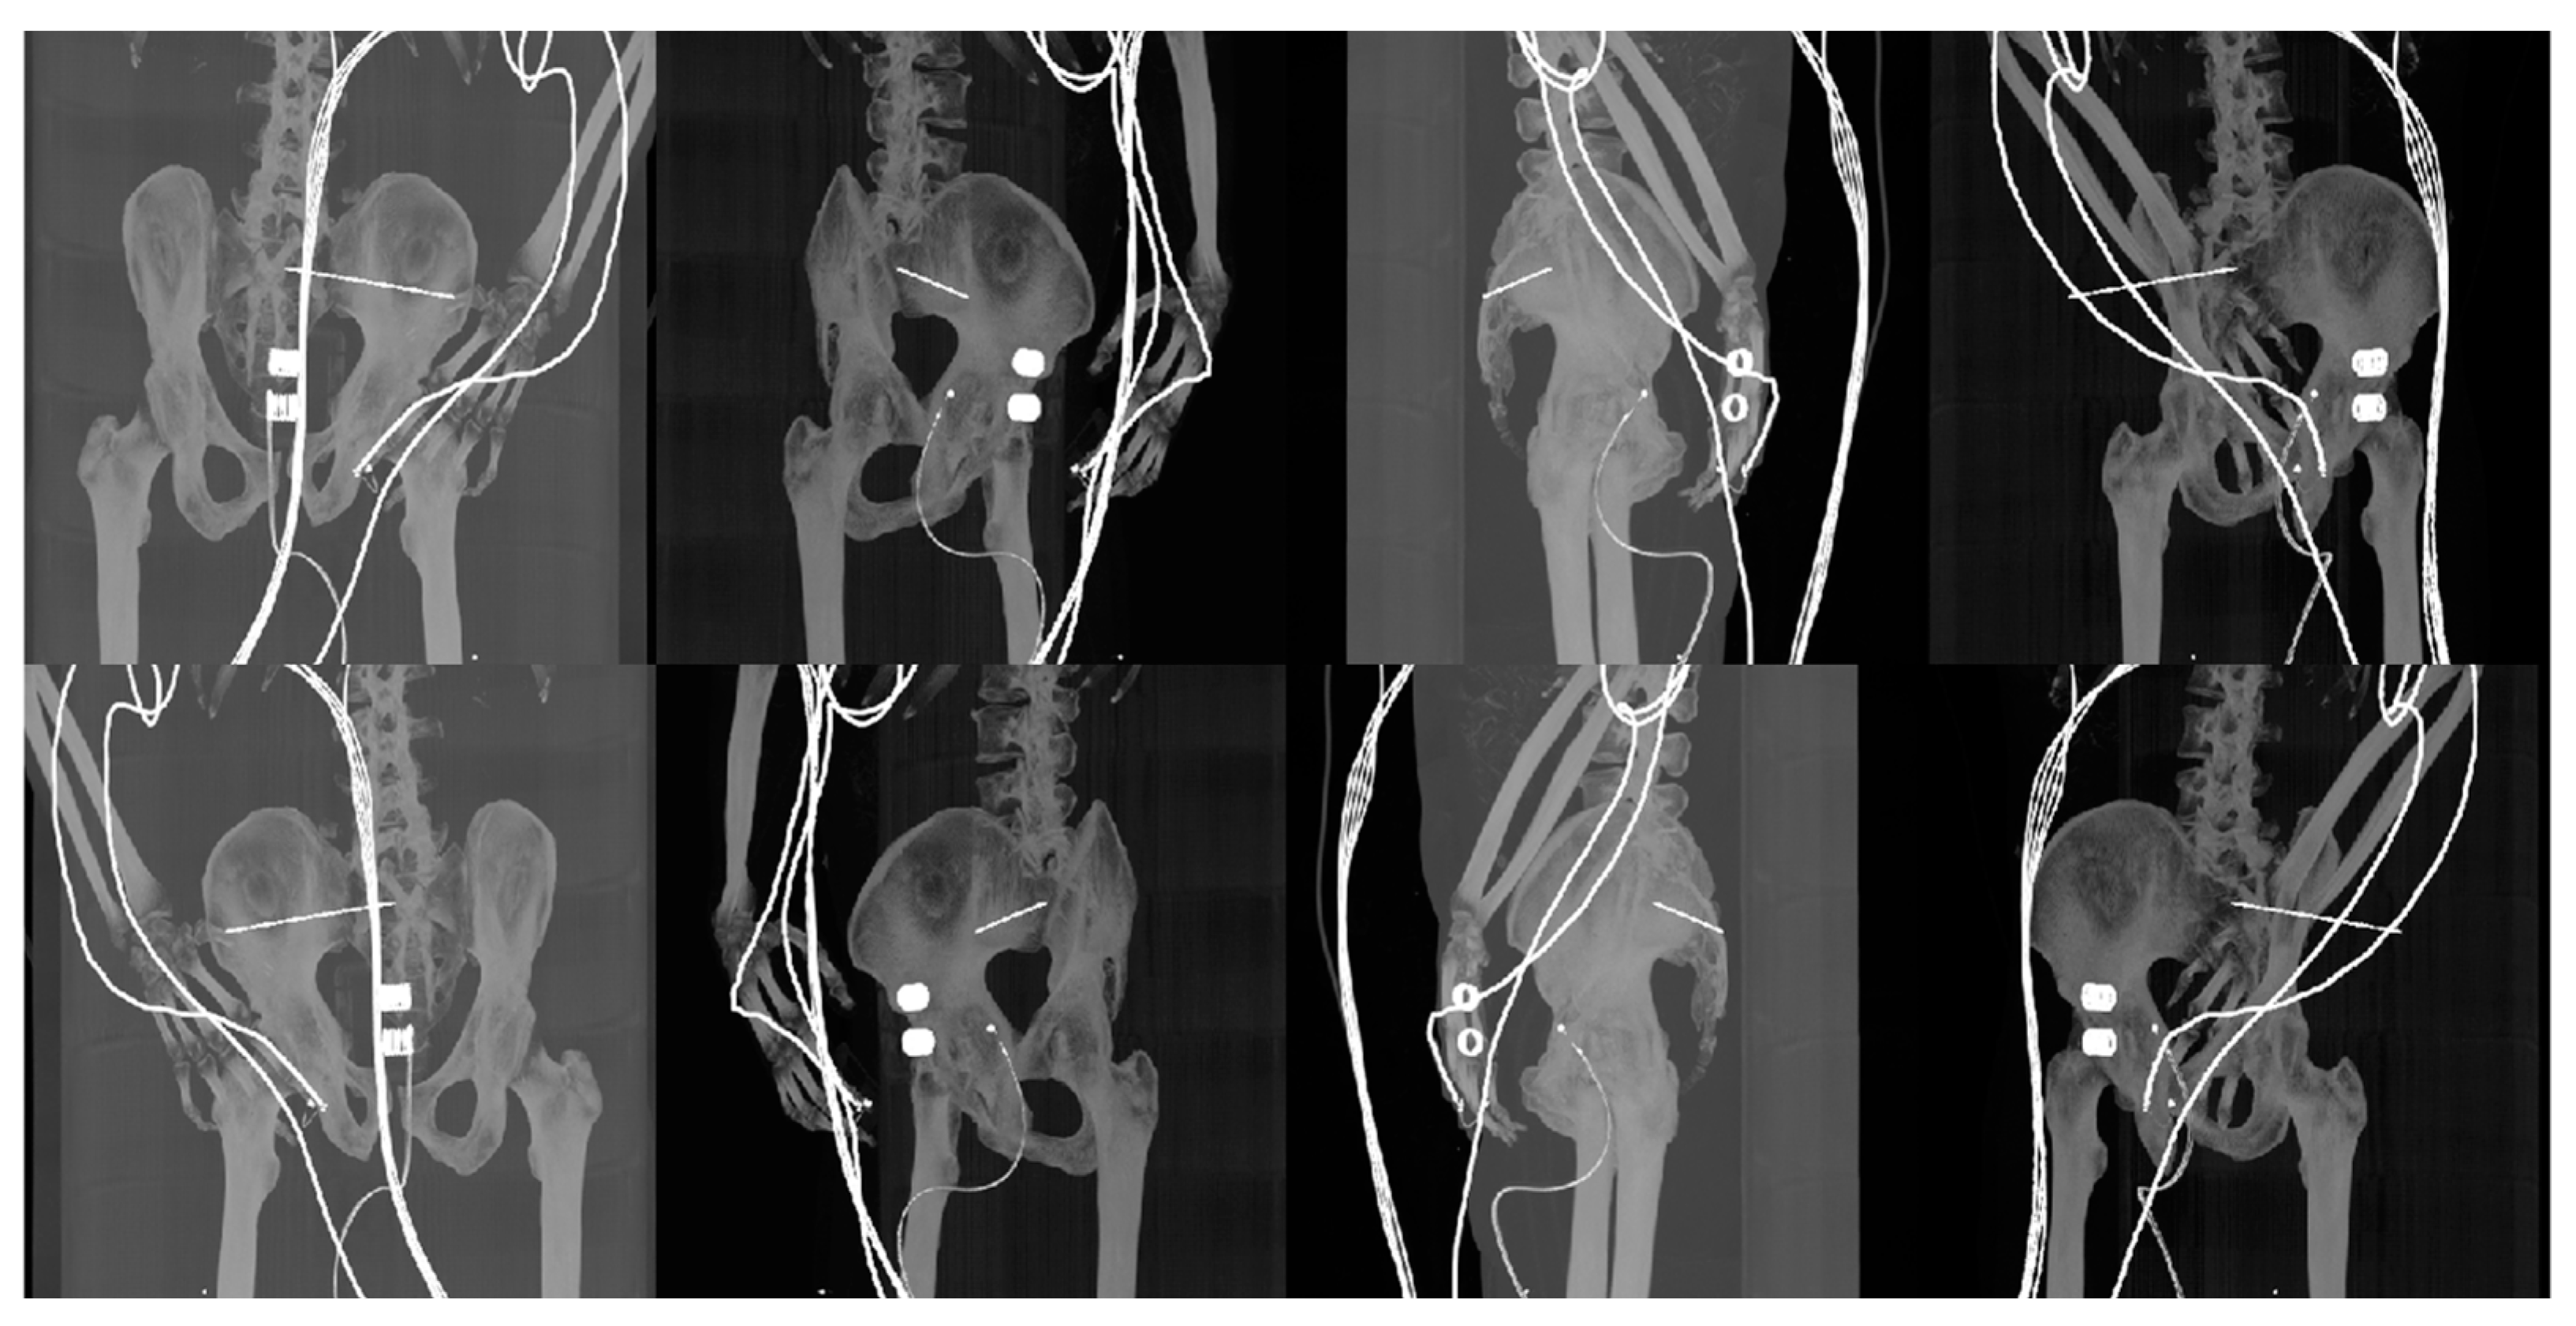

- Reconstructed DDR projections with virtual iliosacral screw

- Generation of digitally reconstructed radiograph (DRR) projections

- Multimodal image registration of DRR projections to a reference X-ray image